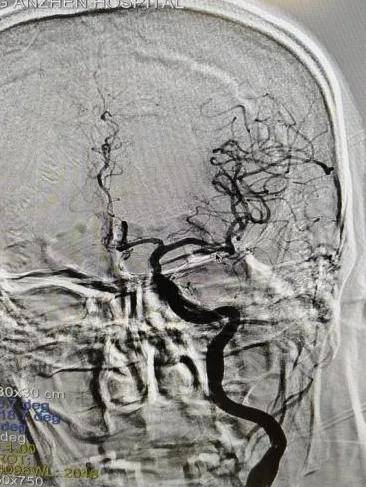

影像科急诊团队完成头颈部血管检查(CTA),结果显示:左侧大脑中动脉M1段急性闭塞!这是给左脑供血的主干血管,堵住了。

图说 / 术前CTA显示左侧大脑中动脉M1段急性闭塞